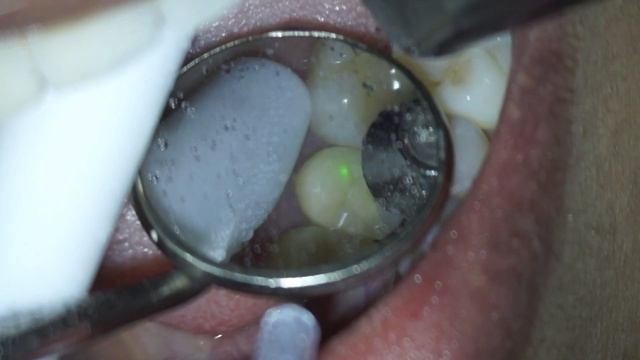

AP Biology: Water is a big dealЦветаевский концерт. Автоор: Вероника ЗахароваПервый городской канал в Калининграде http://1gorodskoi.ru Подписывайтесь на наш канал в YouTube: http://youtube.com/1gorodskoi Группа ВКонтакте: https://vk.com/klgd1gorodskoi #Калининградsubscribe and like the videoPurple Round Rhinestone Slim Magnetic locket with extendable neckalce - For more information check out https://www.joannexx.com//product-page/purple-round-rhinstone-slim-magnetic-locket-with-extenable-neckalcekiz uzatu автор Нуржан 870715117765 ANIME SIMILAR TO HAJIMETE NO GAL Prison School 12 :- https://linkrex.net/rmKx7X4 Rosario + Vampire 26/2 :- https://linkrex.net/F3bco B-gata H-kei 12:- https://linkrex.net/RP4vM0VJ Oregairu 26/2 :- https://linkrex.net/uNooGAu1 Haganai 12 :-https://linkrex.net/J5QIRT7 ▃▃▃▃▃▃▃ ▃▃▃▃▃▃▃▃▃▃▃▃▃▃▃▃▃ ───────── © ᴄᴏᴘʏʀɪɢʜᴛ ɴᴏᴛɪᴄᴇ © ────────── This video is for entertainment purposes only. If you are the original owner of music/content I used in this video & want It to be removed. Please email me at: nightcoreaddict@outlook.com | I'll remove it as soon as I've determined that you're the original owner. Thank you! ▃▃▃▃▃▃▃▃▃▃▃▃▃▃▃▃▃▃▃▃▃▃▃▃ ▲ DISCLAIMER: ▲ I do not own song or any footage used in this video. No copyright intended. Copyright Disclaimer Under Section 107 of the Copyright Act 1976, allowance is made for "fair use" for purposes such as criticism, comment, news reporting, teaching, scholarship, and research. Fair use is a use permitted by copyright statute that might otherwise be infringing. NEFFEX - Take Me Away [Copyright Free]:- https://www.youtube.com/watch?v=qfLikKZ-Kgc Jim Yosef & Anna Yvette - Courage [NCS Release] :-Track: Jim Yosef & Anna Yvette - Courage [NCS Release] Music provided by NoCopyrightSounds. Free Download / Stream: http://ncs.io/CourageYOABONNEZ-VOUS SUBSCRIBE BUSTA JOHN ==================== PEZE LA POU KA ABONNE NAN CHANNEL LA "https://www.youtube.com/channel/UCiKbxgLmxlblwMS3l2myciw/?sub_confirmation=1 ==================== POUR TOUT INFOS 🔴 INFO FONDATION BUSTA JOHN ►► TEL 1514 7550837 🔴 POU CHANNEL ►► TEL 1438-220-9312 MERCI FANMI CHANNEL BUSTA JOHN PÈP HAITIEN PÈP HAITIEN DIASPORA PA BLIYE NOUS18 Mah e Ramzan Kay Din Aur Raat Kay Aamal..!! Maulana Arif Hussain Kazmi A For The Lover Of Ahl-e-Bait (A.S) All Those Who Love Him Are Welcome To Join Us... Subscribe This Channel And Suggest It To Your Friends Jazakallah.. Join Facebook:-https://www.facebook.com/AliZaidy01/ Instagram:-https://www.instagram.com/alii_zaidy/Static X 7Расслабляющая музыка с дождём красивая музыка ПОДПИСЫВАЙТЕСЬ НА КАНАЛ ))) --- https://bit.ly/38hv3kP ***************************************************************** Массажная подушка умини --- https://ali.ski/ghxybS **************************************************************************** Электрическая массажная подушка с инфракрасным нагревом, массажер для шеи, плеч, спины, головы, тела, мусля, мульти релаксационный массажер --- https://ali.ski/Hv1E- **************************************************************************** Маленькая, компактная и удобная – массажная подушка БАУЕР станет прибором который поможет расслабиться в любой момент --- https://fas.st/Bfv03 ***************************************************************************** Прокачай свой мозг Викиум --- https://bit.ly/37I1yZd ******************************************************** ВИКИУМ - https://www.vebante.ru/click?pid=1168... ******************************************************** Пальцевой пульсоксиметр приобрести --- https://ali.ski/xDtEED **************************************************************************** СОЗВЕЩДИЕ КРАСОТЫ --- https://bit.ly/2N99UBu **************************************************************************** КРАСОТА И ЗДОРОВЬЕ --- https://bit.ly/3tosRB5 **************************************************************************** подписывайтесь на канал --- https://bit.ly/3azm0vU **************************************************************************** Санаторно - курортное лечение --- https://bit.ly/3dQmAbP ****************************************************************** Бронирование путевок в санатории --- https://bit.ly/37SrLEy ****************************************************************** Проверенный помощник в поиске авиабилетов, первый и единственный в Рунете метапоиск дешевых авиабилетов --- https://bit.ly/3dRveqH ******************************************************************Decibel Test on these two self emptying robot vacuum docks.Dr.Shiffman removes two zirconia ceramic onlays in minutes using the Fotona Lightwalker laserlive at pats in the flatsВсем известно, что талантливый человек талантлив во всем. Елизавета Леонтьевна была талантливым педагогом, организатором, обладала лидерскими качествами, умением слушать собеседника. Все это ей помогло стать одной из лучших директоров школы. По воспоминаниям её коллег «где бы она ни работала, везде возникала атмосфера доверия, уважения, взаимовыручки. Было интересно работать, в школу ходили с удовольствием. Она растила свое дерево доброты». Наш круглосуточный номер +73519550229 Система поиска захоронений https://evroservis.ooo/burial-search Заказ венков и цветов с доставкой в залы прощания https://promo.evroservis.ooo/venki Официальный сайт компании ЕвроСервис: https://evroservis.ooo Группа ВКонтакте https://vk.com/evroservism Страничка директора компании https://vk.ru/mogulevtcev Адрес: г.Магнитогорск, Челябинский тракт, 3/1 На территории нашего похоронного комплекса расположен храм в Честь Всех Святых https://храмвчестьвсехсвятых.рфAbout 70% of atrial myxomas occur in the left atrium. What do you think of this case?Hey guys, this is my first track and I hope you will enjoy and relax with this track. Sorry for my visualization's failure. I will practice more about editing video. Subscribe my channel and I will bring you to the wonderful world of EDM :)))) Thank you so much. Enjoy ! P/s: The background picture is not mine. The picture from: 123rf.com